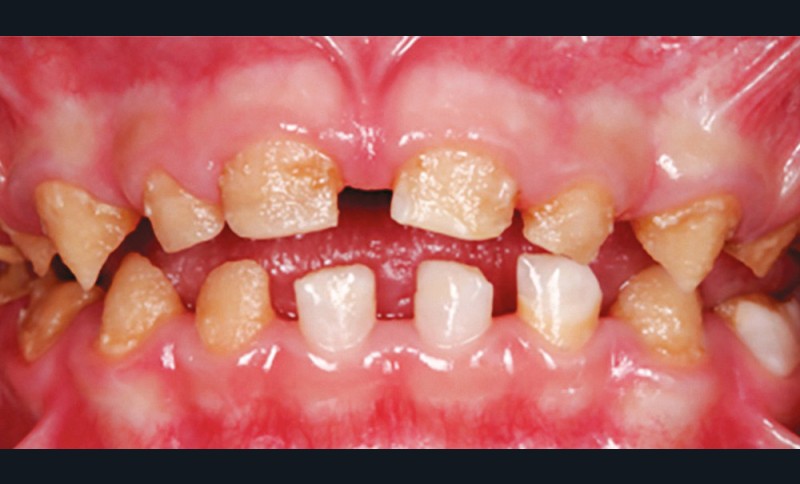

L’amélogenèse imparfaite est le nom donné à un groupe hétérogène de pathologies caractérisées par un défaut inné du développement de l’émail affectant toutes les dents des deux dentures. Ce sont des maladies génétiques dont l’origine est la mutation d’un gène impliqué dans l’amélogenèse. À ce jour, plus de 200 mutations différentes ont été identifiées, ce qui explique des phénotypes très variés [1]. Selon le stade de la maladie, l’émail est hypoplasique (défaut quantitatif), hypominéralisé, ou hypomature (défauts qualitatifs) : il est fin, fragile, tâché ou dyschromique. L’intensité des défauts peut être légère (forme frustre) ou très sévère, allant jusqu’à une absence totale d’émail. Son aspect est altéré par des dyschromies, fractures ou irrégularités de surface (fig. 1-4).